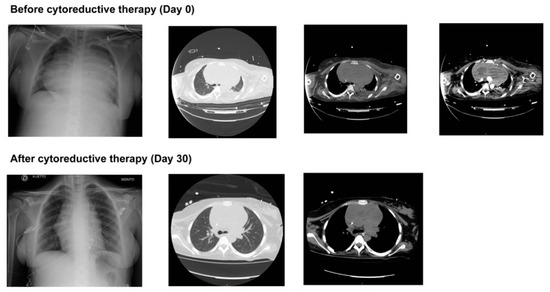

The chest imaging at ICU admission and discharge are shown in Figure 1, showing the reduction in the dimensions of the mediastinal mass. Blood tests of main interest through hospital admission are also shown in Table 1.

Figure 1. Chest imaging at ICU admission and after cytoreductive therapy demonstrates the evolution of both acute lung injury and the reduction of the mediastinal mass.

The incidental discovery of a mediastinal mass that led to the diagnosis of PMBCL was the last challenge we had to face, even though this was the real etiology of all comorbidities. PMBCL is a rare but aggressive non-Hodgkin lymphoma with an incidence of 1 in 6000 pregnancies [2], which in our patient caused superior vena cava syndrome, respiratory distress, and increased thromboembolic risk due to vascular compression and inflammation [4]. The combination of pregnancy-related hypercoagulability and lymphoma-induced prothrombotic state significantly increased the risk of PE, which remains a leading cause of maternal mortality in oncologic pregnancies [46]. In addition, the timely initiation of treatment was crucial [47]. In our case, we had to start the chemotherapeutic treatment even if the patient was intubated, since it was not possible to proceed with weaning and extubation due to mass compression of the airways. In accordance with the current recommendations for aggressive lymphomas in pregnancy, the oncologist opted for the COMP-R regimen (cyclophosphamide, vincristine, methotrexate, prednisone, and rituximab) [20]. As demonstrated in Figure 1, the mediastinal mass was largely reduced, the patient could be weaned off the mechanical ventilator, and the percutaneous tracheostomy was removed.